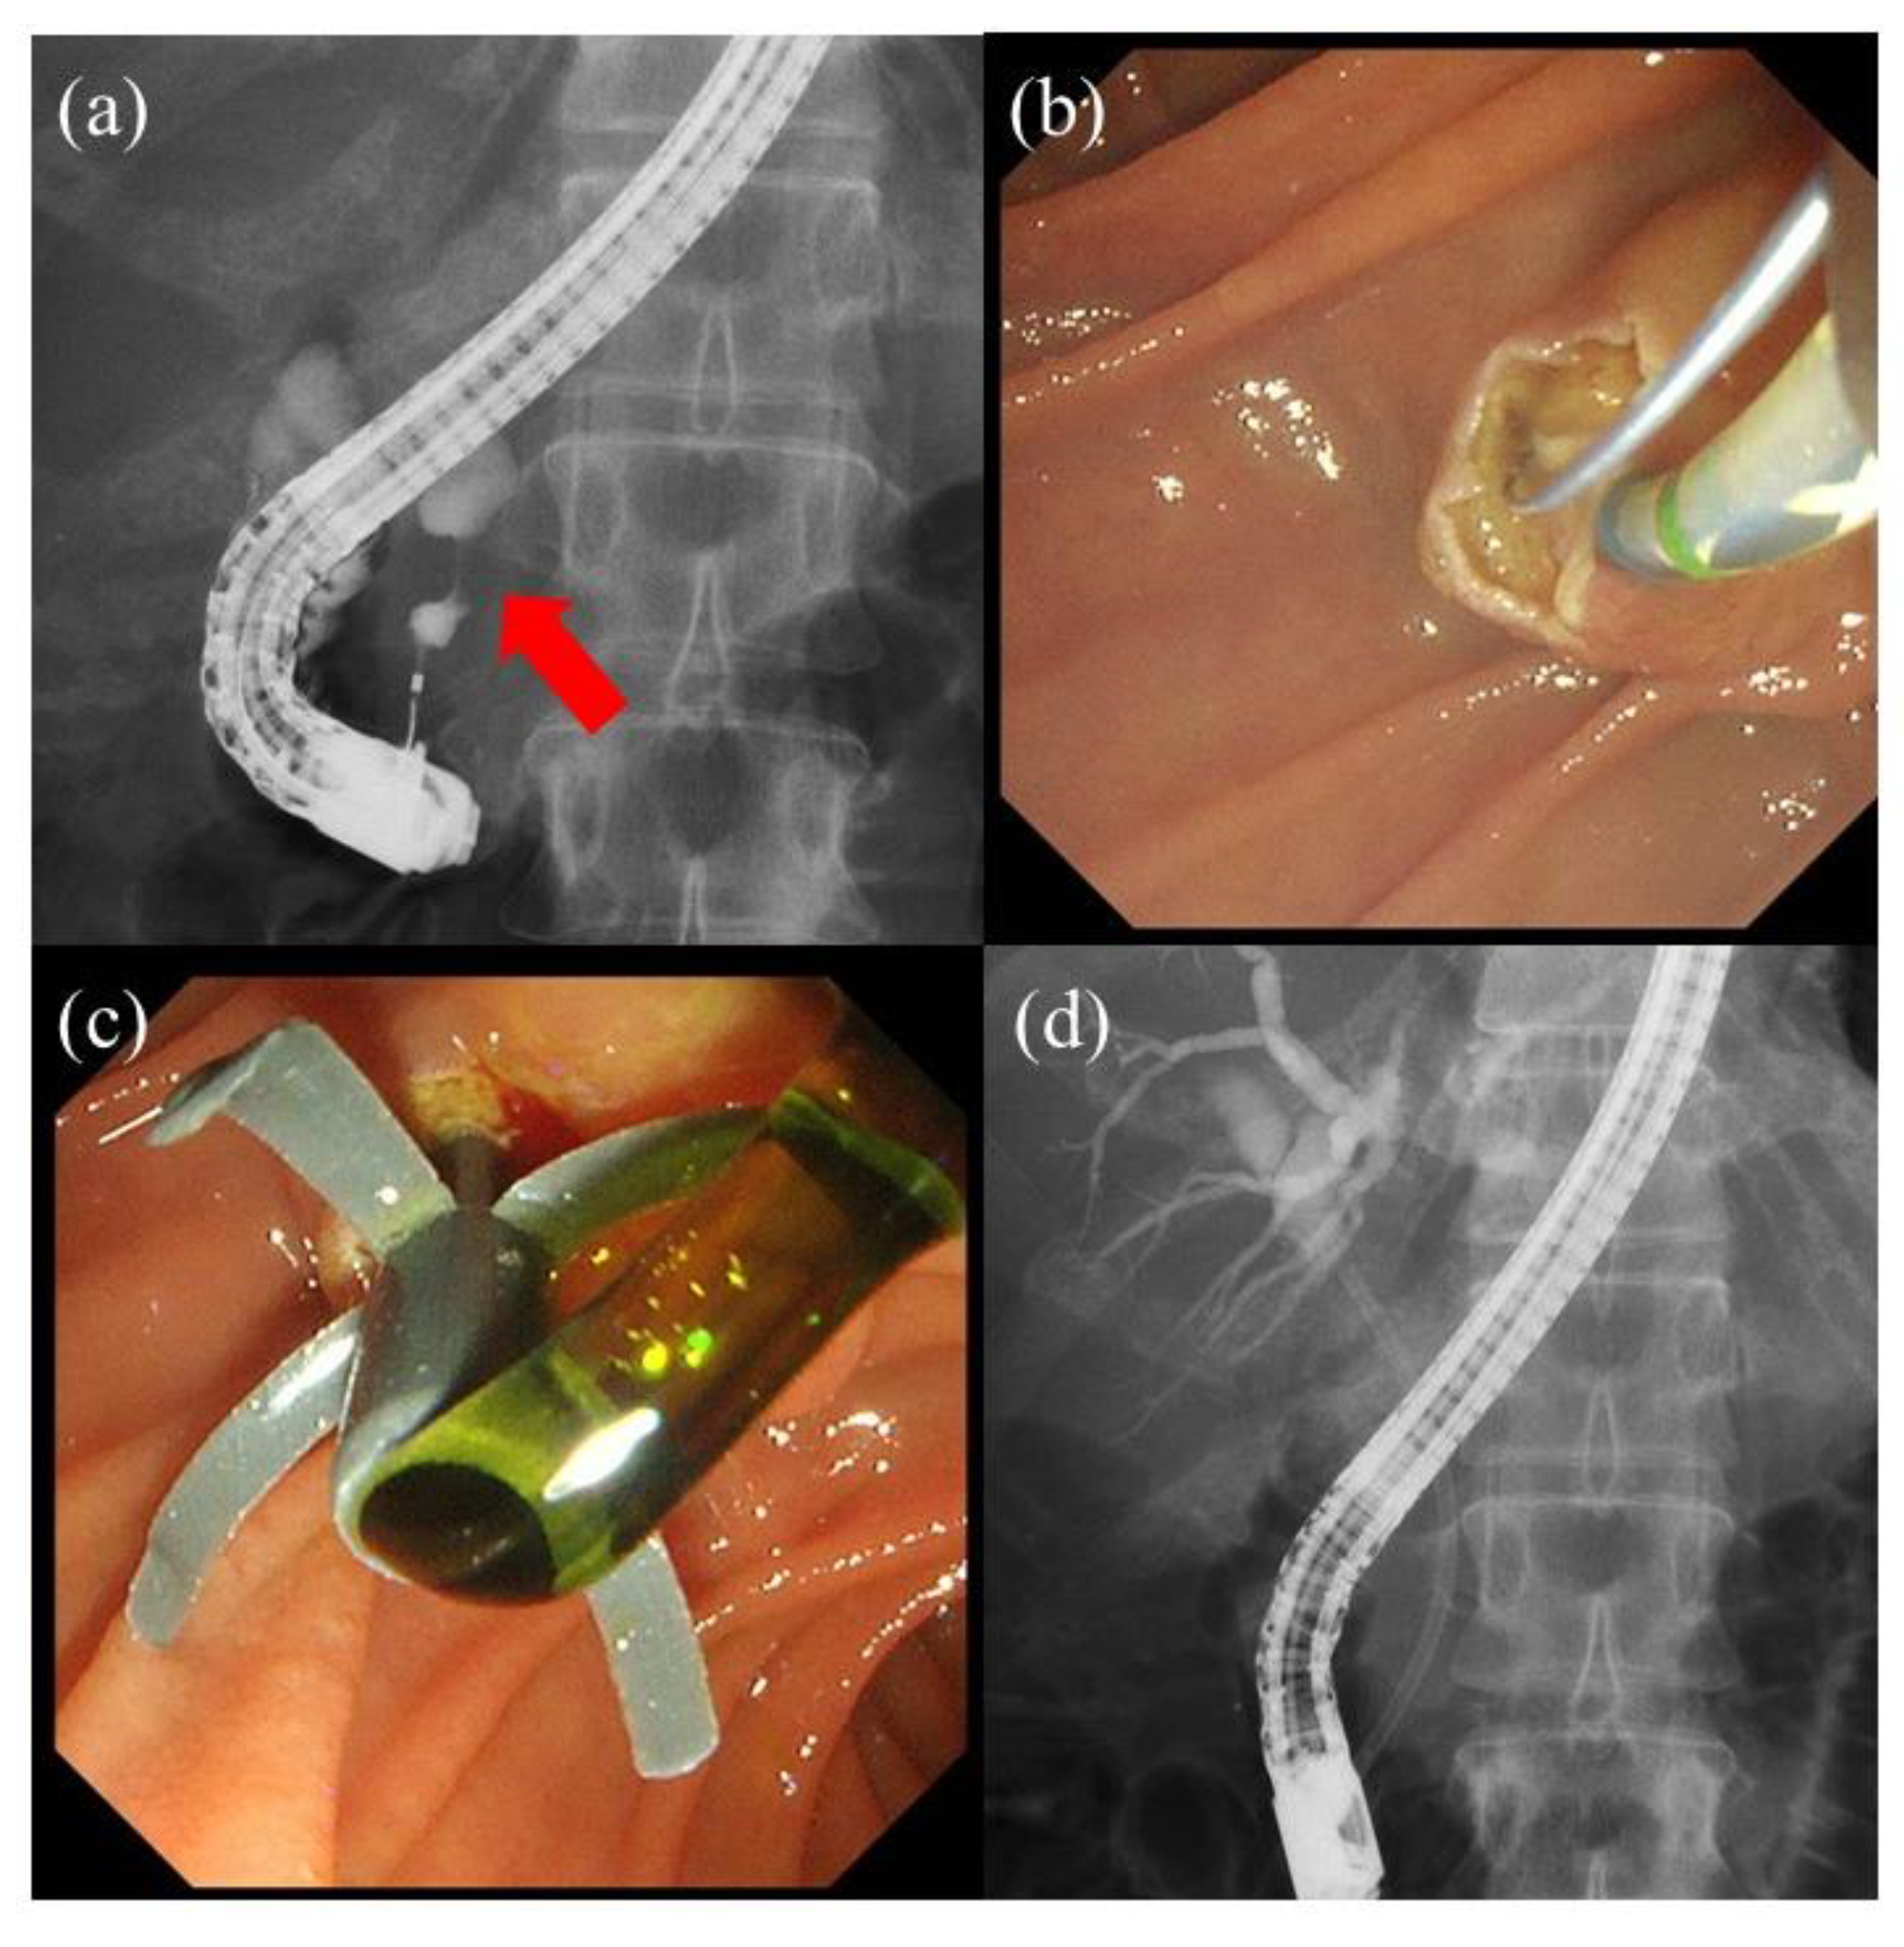

- Kin, T.; Ishii, K.; Okabe, Y.; Itoi, T.; Katanuma, A. Feasibility of biliary stenting to distal malignant biliary obstruction using a novel designed metal stent with duckbill-shaped anti-reflux valve. Dig. Endosc. 2021, 33, 648–655. [Google Scholar] [CrossRef] [PubMed]

- Yamada, Y.; Sasaki, T.; Takeda, T.; Mie, T.; Furukawa, T.; Kasuga, A.; Matsuyama, M.; Ozaka, M.; Igarashi, Y.; Sasahira, N. A novel laser-cut fully covered metal stent with anti-reflux valve in patients with malignant distal biliary obstruction refractory to conventional covered metal stent. J. Hepatobiliary Pancreat. Sci. 2021, 28, 563–571. [Google Scholar] [CrossRef] [PubMed]